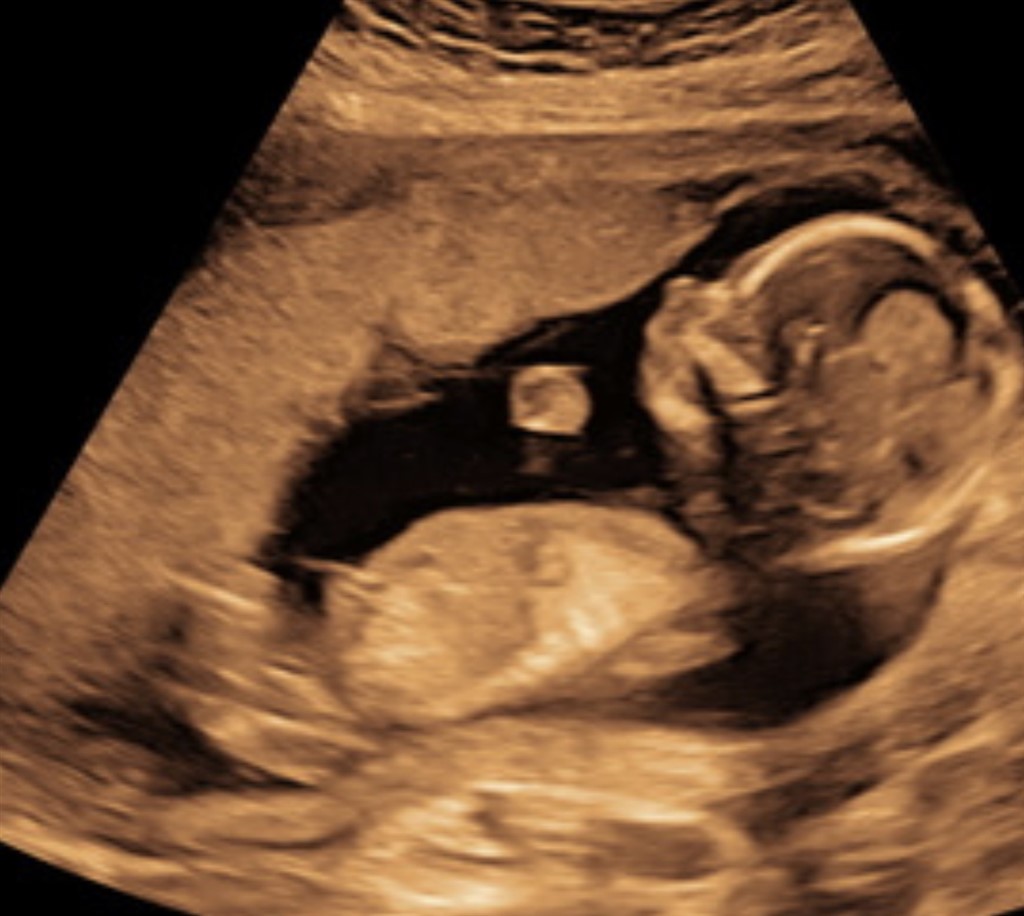

Er der nogen, som kan tyde på disse billeder, at det er en pige?

Jeg skylder lidt forhistorie, beklager. Jeg var til kønsscanning og hun oplyste, at hun var usikker, men troede, at det var en pige. Så blev jeg pludselig selv i tvivl og ville derfor forhøre mig hos jer :-)

Jeg synes det er ok tydeligt med de tre streger for en pige  Tillykke